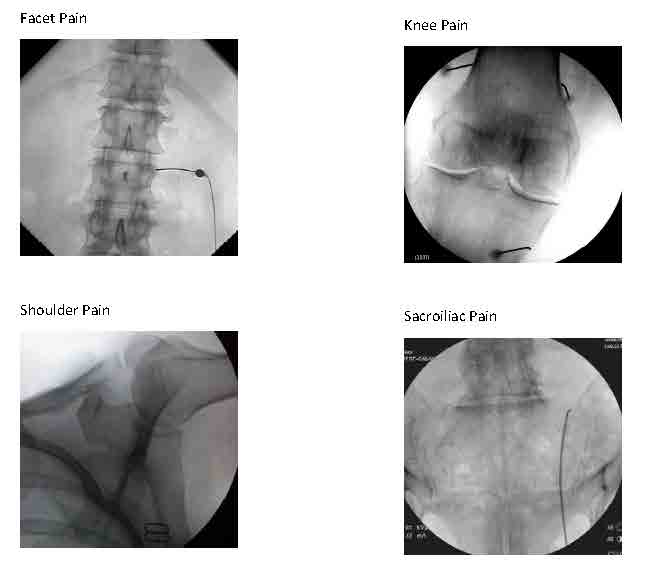

Sacroiliac joint (SIJ) pain is a common source of lumbosacral back pain that we can diagnose and treat with 2 types of fluoroscopically guided procedures:

- Sacroiliac joint steroid injections or

- Blocks of nerves to the SIJ with local anesthetic (for diagnosis) twice to determine if blocking long term with Radiofrequency Ablation/RFA (for treatment) is recommended.

Treatment with RFA tends to last around 9 months on average (give or take 3 months), which could be 2-4 times longer than the SIJ steroid injection. However, the steroid injection requires just one session that combines diagnosis and treatment, where the RFA procedure typically requires 3-4 sessions initially. If successful, future treatments with RFA can be repeated generally without the preliminary diagnostic blocks for recurrence of the same pain.

We can diagnose and treat lumbar facet joint pain due to spondylosis similarly, either with a steroid injection into the joint (intra-articularly) or by blocking small nerves to these joints (medial branch blocks) with local anesthetic diagnostically and, if warranted, with RFA therapeutically (as a treatment).

We can use these same approaches to treat facet pain in the neck less frequently and in the midback rarely.

Other procedures using fluoroscopic guidance are evolving. Genicular nerve blocks that involve the usual 2 sets of diagnostic anesthetic blocks followed by blocks with RFA can be very helpful in patients with knee osteoarthritis that is either inoperable or has already failed knee joint replacement surgery. RFA nerve blocks to other joints such as the shoulder and hip for osteoarthritis are in development.